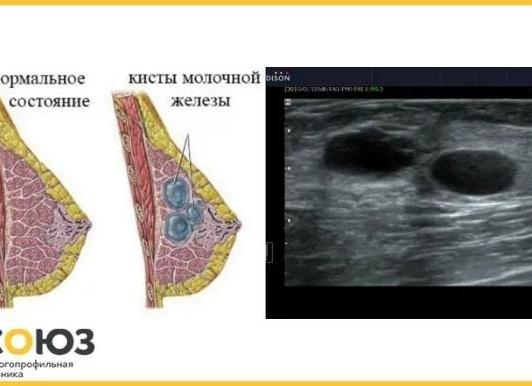

Фиброзно-кистозные образования в молочной железе, видимые на аппарате УЗИ

Эхогенность образований молочной железы определяется степенью плотности (клеточности) тканей и различного их видения на мониторе аппарата УЗИ.

1. Анэхогенное образование в молочной железе – это киста, которая диагностируется при обследовании УЗИ молочных желез, а опасность данного заболевания выявляется при помощи пункции и цитологического исследования её содержимого.